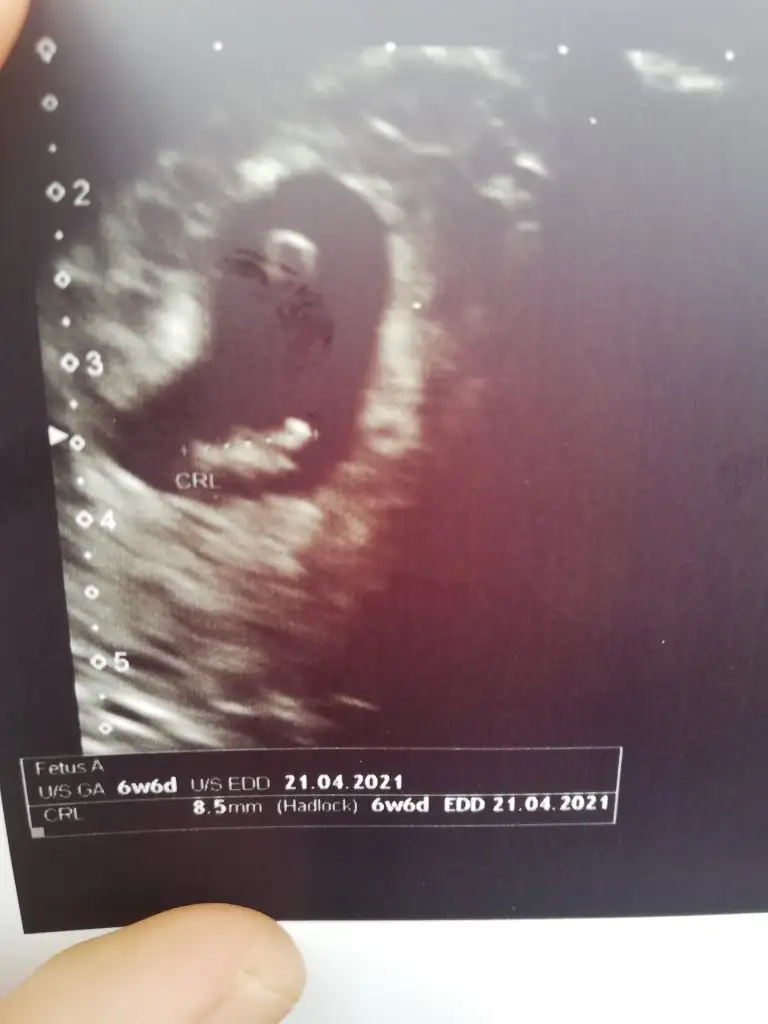

Bende kız hissediyorum bakalım ne çıkacakKız buna göre tabiki en iyi 11 12 13 haftalar olmalı

Bebek sol da değil mi canım.Hani kiz sağda erkek solda yazıyor ilk sayfada.Kız buna göre tabiki en iyi 11 12 13 haftalar olmalı

Yolk saç neredeyseBebek sol da değil mi canım.Hani kiz sağda erkek solda yazıyor ilk sayfada.

Birde vajinal USGBebek sol da değil mi canım.Hani kiz sağda erkek solda yazıyor ilk sayfada.

Anladım vajinal olduğunu görmedim çok pardon.Bu yolk sac olayı falan beni aşar.Birde vajinal USG

Kız gibi buna göreÇok teşekkür ederim. Aynı gün çekilmiş bir usg daha var. Orda da sağa yakın görünüyor.

Kese için büyük nub için küçük 11 12 13 haftalar olmalı9 haftalık resim ikra meyra yorumlayabilirmisiniz cinsiyetini:)

Ama haftasında önemli 6+hafta olmalıBende kız hissediyorum bakalım ne çıkacak